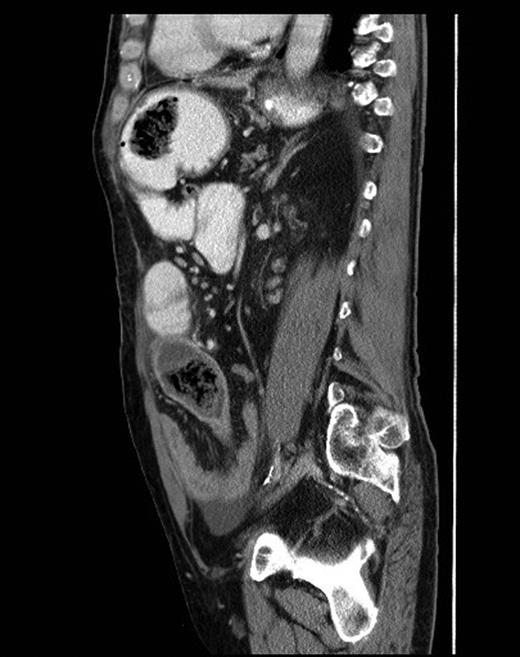

Sagittal CT scan view showing foreign bodies in the stomach and the ileum with transition point in the small bowel.

At laparotomy, a previous gastrojejunostomy with dense adhesions in the upper abdomen was found. An obstructing hard foreign body was palpable in the ileum with dilatation of the proximal small bowel loops. A larger similar foreign body was mobile and palpable within the stomach. (Fig. 3) Both foreign bodies were removed through an enterotomy and gastrotomy, respectively, and the bowel was decompressed. After limited adhesiolysis, the abdomen was closed en mass repairing the midline hernia defect.